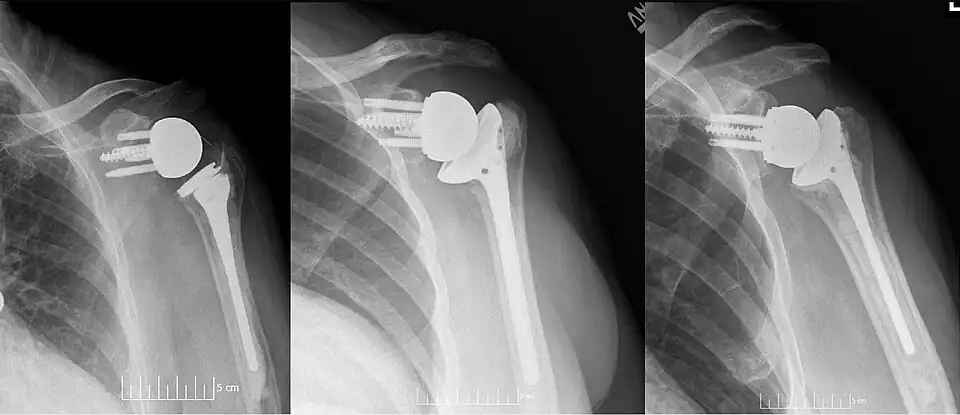

Os implantes modernos de ombro reverso consistem em várias partes. No osso da escápula, há uma placa de base metálica que se desenvolve no osso da glenoide nativa, parafusos e/ou pinos que a mantêm no lugar e um componente metálico redondo de "glenosfera" que é acoplado à placa de base por meio de vários mecanismos diferentes. No osso do úmero, normalmente há um revestimento de polietileno côncavo que se articula com a glenosfera convexa e é fixado a uma haste umeral que cresce no úmero nativo ou é cimentada no lugar. Dentro dessa estrutura básica, há diversas variações diferentes de implantes e, até o momento, não há consenso sobre qual projeto é superior, embora vários estudos tenham demonstrado alguns benefícios de determinadas combinações.[9][10][11] Um desses sistemas modernos de implante de ombro reverso é o AltiVate Reverse. Mais informações sobre esse sistema podem ser encontradas no site da DJO.